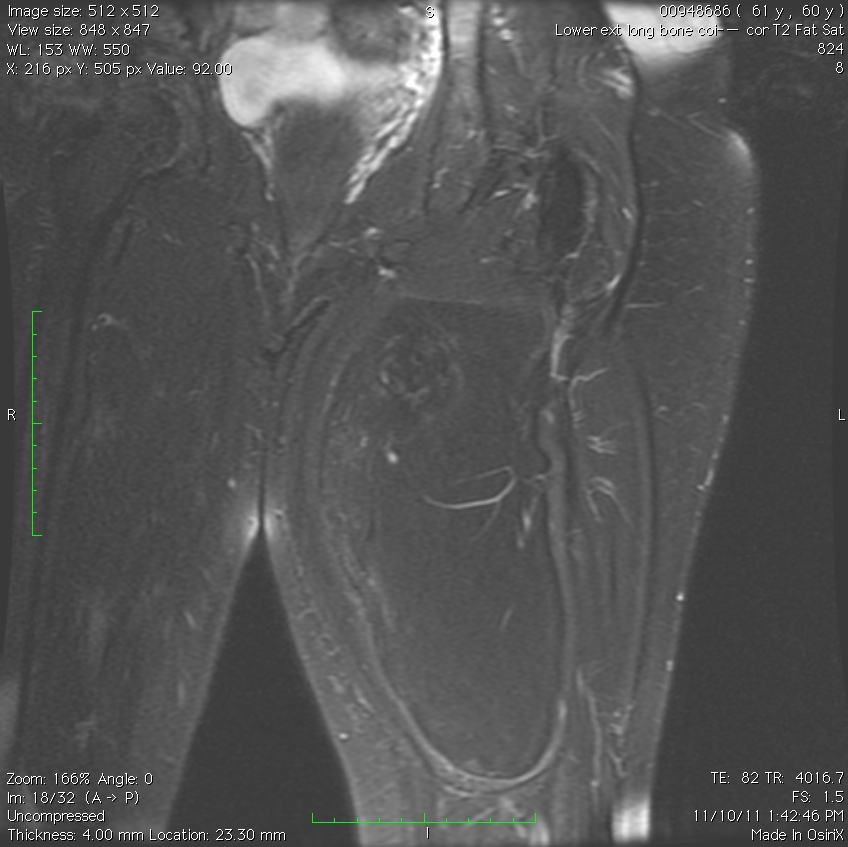

MRI

• Follows the signal characteristics of subcutaneous fat on all sequences

• T1: High Signal

• T2: Intermediate Signal; Low Signal with Fat Suppression

• Minimal or No enhancement with gadolinium

Fig. 1A, 1B, 1C, 2A, 2B, 2C: MRI of a lipoma: T1- weighted images shows an homogeneous mass in the posterior compartment of the thigh with high signal, saturates on fat saturated sequences with no or minimal enhancement. On T2-weighted images demonstrate an intermediate signal on FSE T2, saturates (becomes dark) on fat saturated sequences.